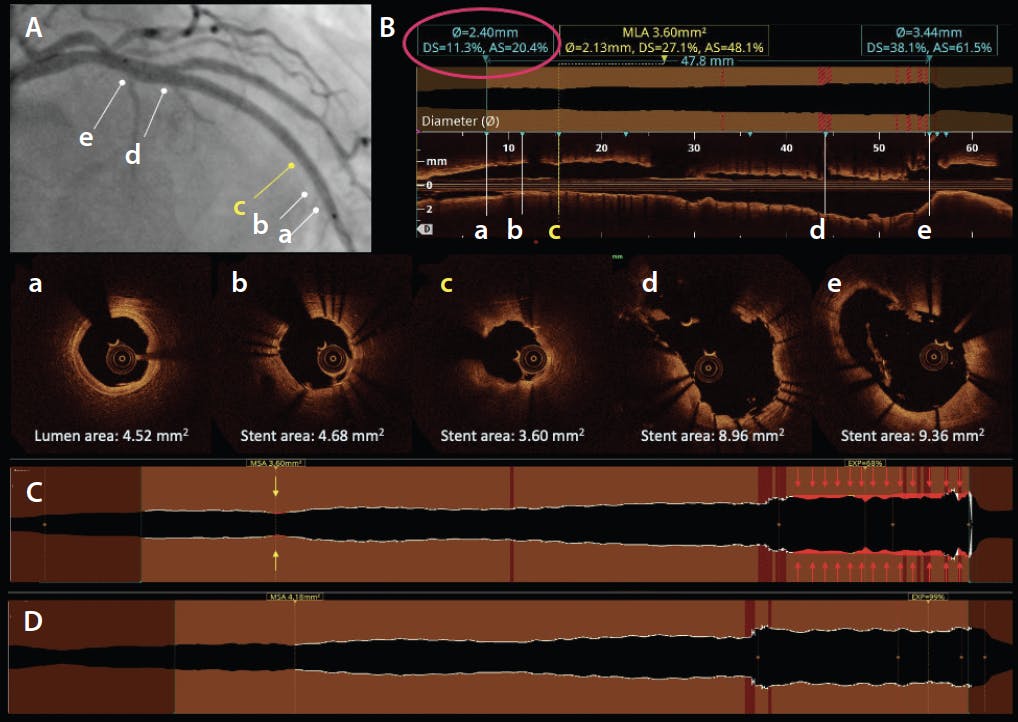

It is our opinion that each of the previously mentioned expansion criteria has inherent limitations. They can underestimate expansions in tapered vessels and do not reflect global stent expansions or capture multifocal regions of underexpansions. A recently proposed volumetric stent expansion creates an ideal lumen profile along the stented segment resultant from an adaptive reference profile computed using the natural vessel taper due to side branch ramifications, according to the Huo-Kassab model. A major side branch is defined as having a radius > 0.50 mm. Each frame along the stented segment is assigned a normalized expansion index, calculated as (actual in-stent lumen area/ideal lumen area) X 100. The minimum expansion index (MEI) is automatically identified at the site with the lowest expansion index. This model (incorporated in the OCT software as the “tapered mode”) showed a better correlation with post-PCI FFR than the conventional relative expansion. Multivariable analysis identified severe (≤ 73.3%) MEI as the only independent predictor of device-oriented composite endpoints, while absolute MSA and relative expansion were not. Future prospective studies are necessary to establish the prognostic role of MEI.31 Figure 3 presents the various ways of assessing stent expansion.

Figure 3. Assessment of stent expansion. A 2.75- X 48-mm stent was implanted in the proximal-to-mid left anterior descending artery (LAD; provisional strategy to the first diagonal branch). Postdilatation of the stent was performed with a 2.75- X 12-mm noncompliant balloon inflated at 28 atm. Proximal optimization was performed with a 3.5- X 8-mm noncompliant balloon inflated at 24 atm. Post-PCI angiogram recorded during OCT acquisition (A). Lumen profile and longitudinal views of the post-PCI OCT (B). Images “a” through “e” indicate OCT cross-sections of the sites indicated on the angiogram and longitudinal images. The MSA was 3.60 mm2 (cross-section c), which corresponded to 20.4% underexpansion compared to the distal reference lumen area (4.52 mm2; cross-section a). The novel volumetric expansion mode (C). The MSA is located in the distal stent segment (double yellow arrows). However, the MEI measured 68% in the stent segment proximal to the bifurcation (red arrows). Volumetric expansion is color-coded as white (MEI > 90%), yellow (MEI, 80%-90%), and red (MEI < 80%). Note the long segment of underexpansion in the proximal stent was far away from the MSA, in a region where the stent areas were much larger than the MSA and would not be captured by conventional ways of quantifying stent expansion. Optimization with 3- X 12-mm and 3.75- X 8-mm noncompliant balloons was performed in the distal and proximal stent segments, respectively. Significant improvement of the MSA (4.18 mm2) in the distal stent segment and resolution of the underexpansion in the proximal stent segment (MEI, 99%) (D). AS, area stenosis; DS, diameter stenosis; EXP, expansion; MLA, minmum lumen area.